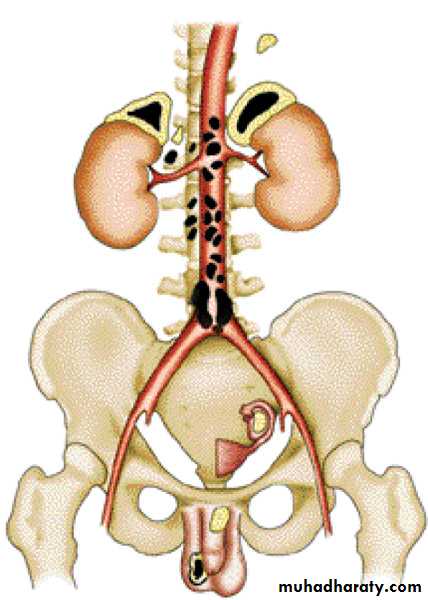

Adrenal (suprarenal) gland: cotrex and medulla. Stain H&E .